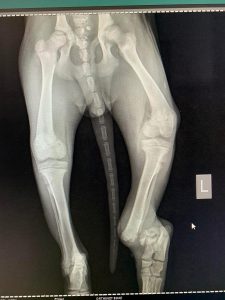

Psi i mačke su aktivne životinje sklone ortopedskim povredama, a najčešći uzroci su saobraćajne nesreće, padovi, udarci.

Genetika i degenerativni procesi često igraju ključne uloge u razvoju različitih problema sa kostima, zglobovima, ligamentima i hrskavicom, što može biti prisutno od rođenja ili se razvija tokom rasta životinje. Ortopedske povrede ozbiljno utiču na kvalitetu života ljubimaca, ali uz pravovremenu dijagnozu i terapiju se mogu uspješno oporaviti.

- Liječenje prijeloma kostiju, uključujući intraartikularne frakture